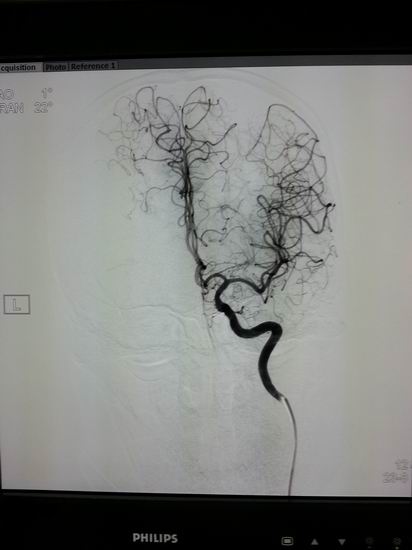

名称:高档数字减影、血管造影系统 Allura Xper FD20

主要功能:采用大平板科技,结合2K影像链,提供极佳图像细节解析能力,1250mA成像能力与“透心凉”高散热球管,“Refresh light”技术消除动态采集时的鬼影,图像质量更高。